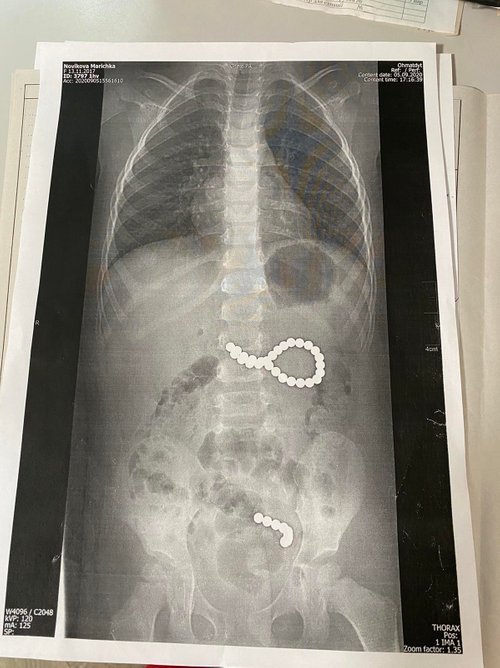

Дівчинку доставили до Львівської лікарні Охматдит з Дрогобича. Лікарі відразу зробили дівчинці знімок і виявили, що дев'ять кульок під впливом магнітного поля створили ланцюг, а ще 27 – створили неправильне коло і потрапити в кишківник просто не могли. Було прийнято рішення оперувати дитину негайно, пише видання Zaxid.net.

"Дев'ять кульок, які дитина проковтнула у п'ятницю, створили ланцюжок, оскільки було сильне магнітне поле. І вони пройшли зі шлунка в тонкий кишківник. А ті 27 магнітних кульок, які дівчинка проковтнула в суботу, створили неправильне коло і їх потрібно було негайно дістати. Кульки були діаметром 4 мм, найімовірніше з якогось конструктора", - розповіла хірург Охматдиту Оксана Горбач.